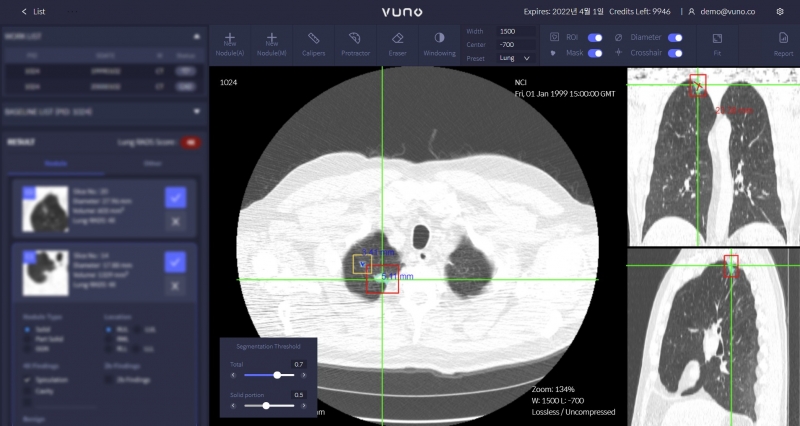

뷰노메드 흉부 CT AI는 폐 CT 영상에서 폐 결절을 검출하고 결절에 대한 정량적인 정보를 제공하는 솔루션이다. 절편(slice) 영상 재구성 기술인 Super Resolution(SR) 등 기술적인 차별성과 우수성을 인정받아 제22호 혁신의료기기로 지정됐다.

Super Resolution은 두꺼운 절편 CT 영상을 1mm 얇은 절편 CT 영상으로 재구성하는 기술이다. 3mm, 5mm 등 두꺼운 절편에서 탐지하기 어려운 작은 크기 결절이나 악성으로 발전할 가능성이 높아 추적관찰이 필요한 반고형결절을 정확하게 탐지할 수 있도록 돕는다.

회사에 따르면 해당 기술을 활용하면 3mm, 5mm 등 두꺼운 절편으로 흉부 CT 촬영을 하는 의료기관이 기존 촬영방식을 유지하면서도 더욱 안전하고 정확한 폐암검진을 수행할 수 있고, 환자로서는 얇은 절편 CT 촬영보다 방사선 노출 위험을 낮출 수 있는 것이 장점이다.